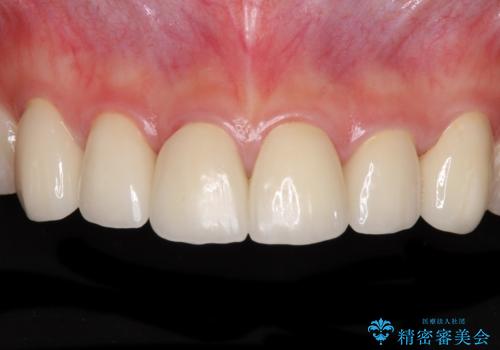

- コンポジットレジンによる治療で継ぎ接ぎだらけになってしまった前歯を綺麗にしたいとのことで来院された患者様です。

必要に応じて根管治療を行い、前歯6歯をオールセラミッククラウンで補綴することとしました。

普段は海外在住であり、出産のための一時帰国を利用して短期集中治療を行いました。

自身の出産で大変な時期にもかかわらず、スケジュール通りに通院いただき、望まれたとおりの口元に仕上げることができました。